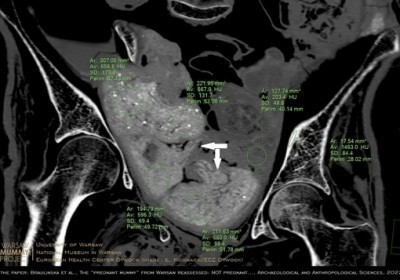

Mumia egipska z Warszawy nie była w ciąży - w jej miednicy znajdują się... pakunki